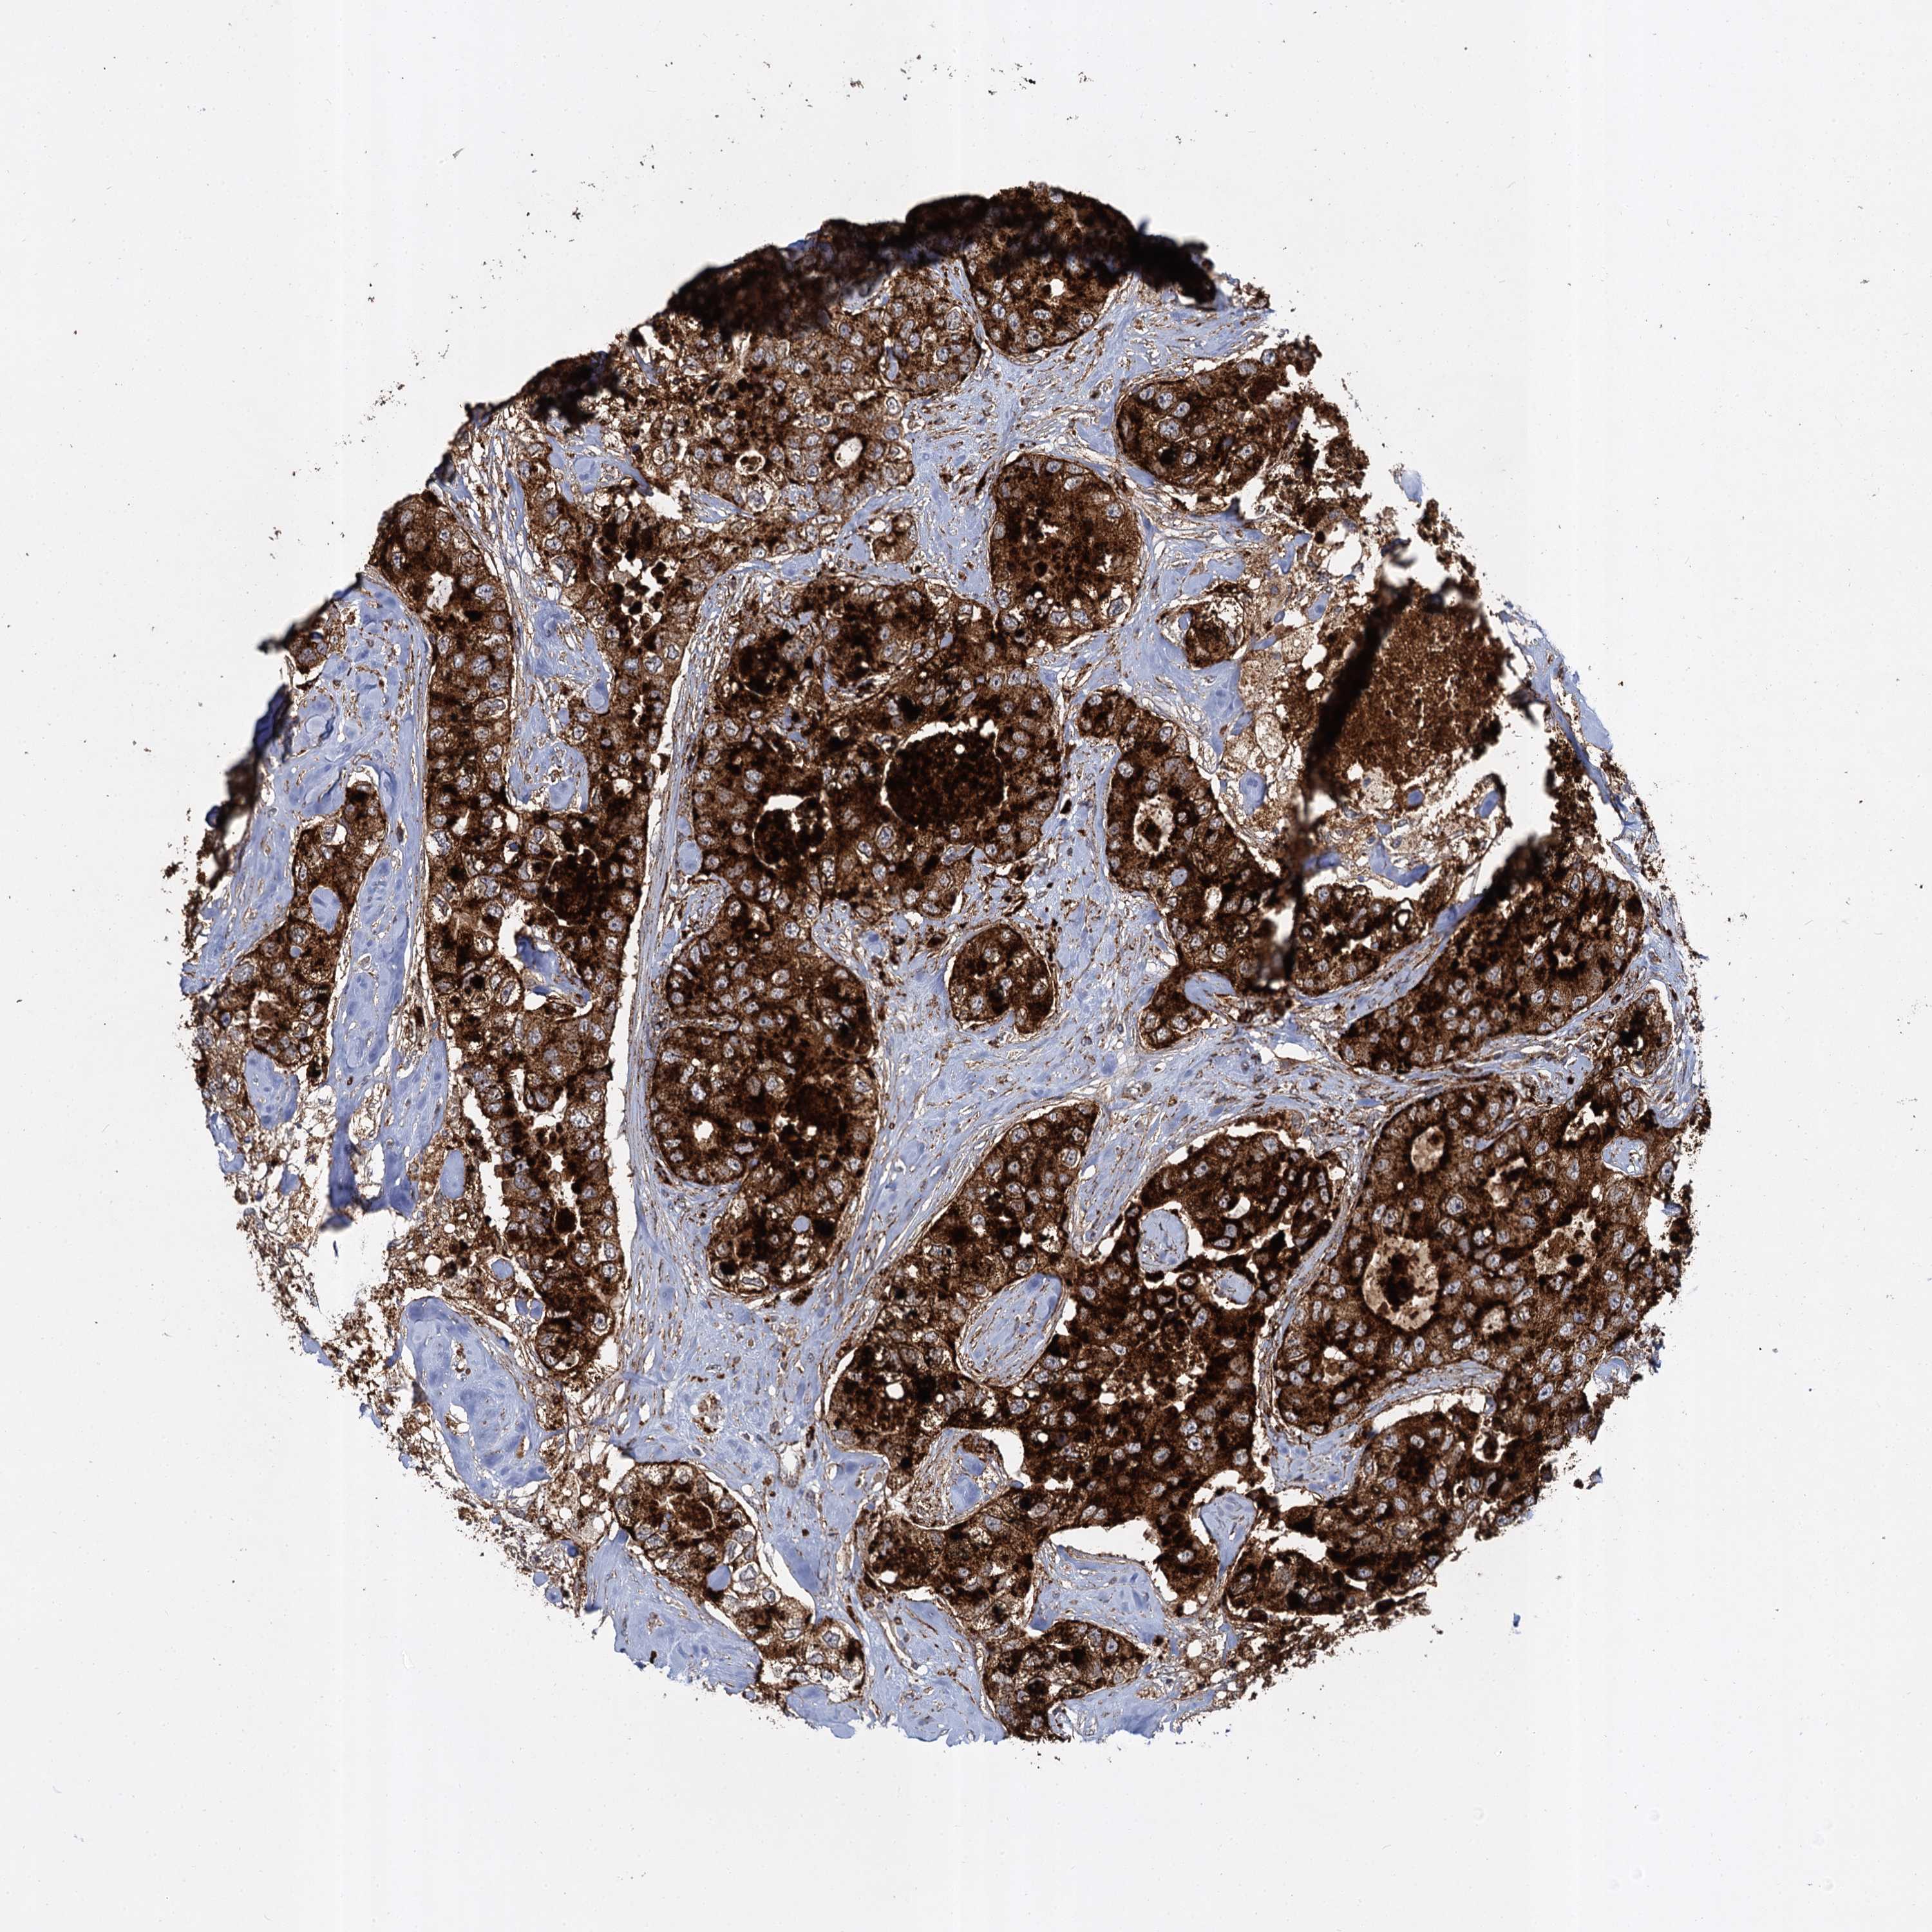

CANCER BREAST CANCER Show tissue menu

BRCA TCGA BRCA VALIDATION PROTEIN EXPRESSION

ANTIBODIES

AND

VALIDATION